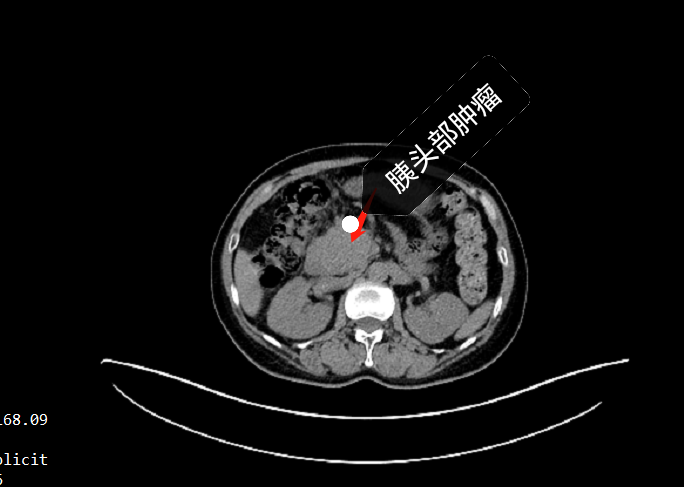

這是我們一個月之前治療的一個晚期胰腺癌肝轉(zhuǎn)移,病人已經(jīng)70歲了,由于有肝轉(zhuǎn)移,無法手術(shù),胰腺癌對放化療不敏感,經(jīng)過咨詢后最終采用我們治療方案:先海扶刀減瘤,消滅原發(fā)病灶和肝臟腫瘤,再聯(lián)合化療來控制維持。?海扶手術(shù)很順利,術(shù)后第二天就正常出院,現(xiàn)在海扶刀治療后40天,病人恢復(fù)良好,沒有特別不舒服,腫瘤標(biāo)志物ca199從治療前的898,現(xiàn)在已經(jīng)下降到197。

這是我們今年4月份治療的一個晚期胰腺癌,腫瘤侵犯十二指腸,膽管和血管,腫瘤標(biāo)志物ca199大于12000,無法手術(shù)切除?;颊吲畠涸趪猓私獾胶7龅吨委熀?,帶上患者到我們中心選擇海扶刀治療,術(shù)后口服化療藥控制,現(xiàn)在病人已經(jīng)快10個月了,腫瘤控制良好,ca199也降到了5600,恢復(fù)良好。

這是我們?nèi)ツ?月份治療的一個早中期胰腺癌,病人已經(jīng)80歲了,當(dāng)時體檢發(fā)現(xiàn)胰腺鉤突部腫瘤,至浙江省邵逸夫醫(yī)院就診,準(zhǔn)備是進(jìn)行傳統(tǒng)的手術(shù)切除,由于患者年齡大,腫瘤靠近腸系膜上動脈,考慮手術(shù)風(fēng)險高,術(shù)后并發(fā)癥多,最終選擇了無創(chuàng)的海扶刀治療。術(shù)后予以小劑量化療藥化療維持,現(xiàn)在復(fù)查,顯示腫瘤壞死依然明顯,病人也沒有特殊不適,生活質(zhì)量得到了最大化的保證。對比患者同期發(fā)現(xiàn)的胰腺癌患者,目前患者情況是屬于比較良好的。胰腺癌是惡性程度非常高的惡性腫瘤,傳統(tǒng)治療方案主要是手術(shù)加化療,但是手術(shù)需要切除胰腺、十二指腸,重建膽道、消化道等,術(shù)后并發(fā)癥多,生活質(zhì)量比較受影響。海扶刀治療屬于微無創(chuàng)治療,不用開刀,直接燙死腫瘤,達(dá)到減瘤止痛,延長生存期的目的,甚至部分患者能達(dá)到治愈的效果。